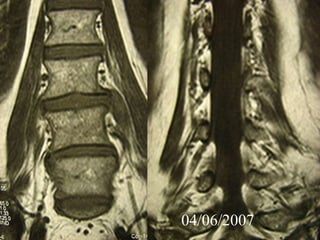

4th case

D.N.

M 61– Cardiologist

Symptoms

 Severe Neurologic deficit

 Intensive Thoracic-lumbar Pain

 High fever

Laboratory

 Neutroph. ↑

 SR 60

PMH

 Heavy smoker

 Diabetes melitus

 Recent Elbow Furuncle (untreated)

04/06/2007